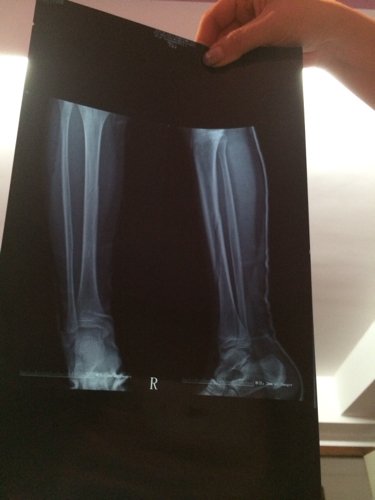

我右小腿胫骨腓骨骨折 现在在家养的,鼓膜已经长出来了 打好石膏了 还会不会错位了? 点击展开 匿名用户 2014-02-22 20:57 为您推荐: 其他回答 病情分析: 您好,根据您的描述,您的情况是胫骨骨折 指导意见: 从您上传的片子来看,您是一个斜性骨折,骨折没有什么移位,您现在的治疗是合理的,一般是不会移位的。 匿名用户 2014-02-22 21:06 相关问题 我左小腿下左胫骨骨折己经两个多月,昨日己拆石膏,但内侧位… 小腿胫骨骨折打石膏后复查有错位,宝宝才两岁半怕以后有影响 一周六个月的宝宝小腿胫骨螺旋骨折无错位21天石膏拆除以后会影响走路吗